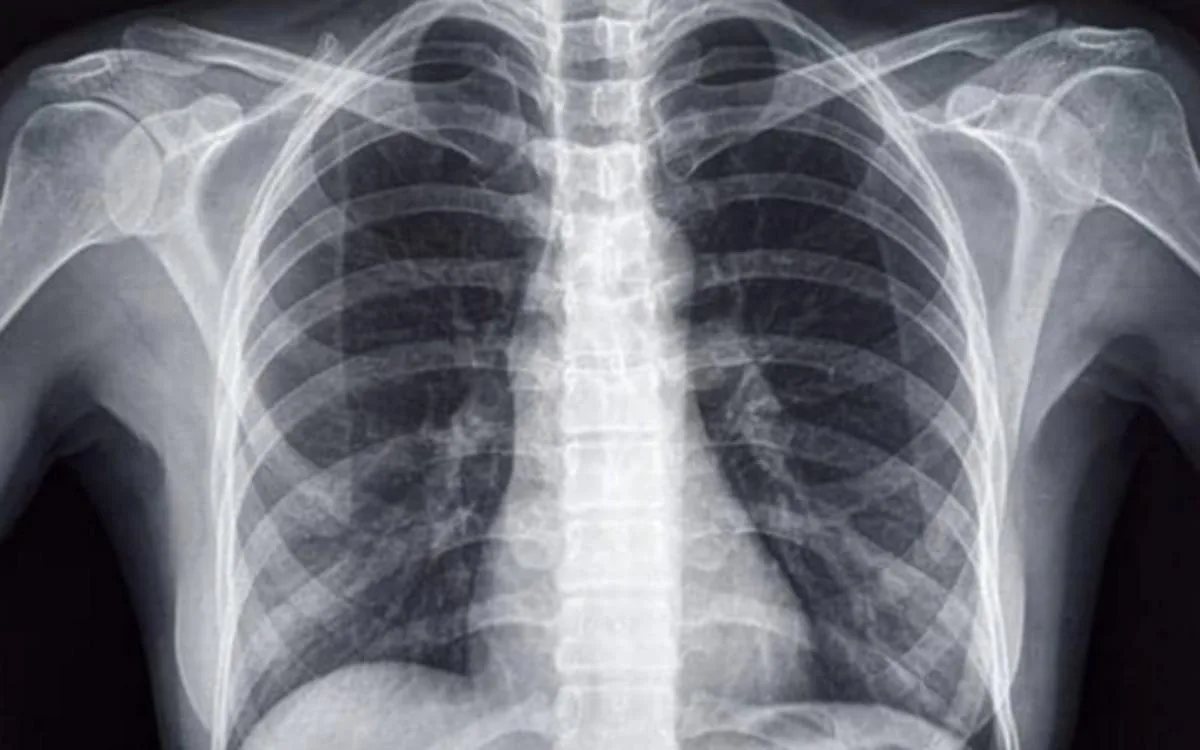

Appelée « situs inversus », cette anomalie congénitale rare et complexe se transmet de façon génétique et héréditaire ou peut se greffer sur d’autres pathologies. « C’est une anomalie dans laquelle un ou plusieurs organes sont situés du côté opposé à celui qu’ils occupent normalement. Cette condition se produit avec une fréquence de seulement 0,01 % et peut concerner la totalité des organes, ou n’être que partielle en cas de “situs inversus incomplet” », explique à la MAP, Fatiha El Ghadouri, le médecin traitant de l’adolescente.

La spécialiste précise que « l’absence de malformations dans les organes permet aux personnes concernées de mener une vie normale, sans aucun problème de santé, ce qui rend la découverte de ces cas souvent fortuite », ajoutant qu’en 30 ans de service, elle n’a rencontré que trois cas de cette anomalie congénitale. Dr. Abdeladim Chaquibi, chirurgien général, fait observer pour sa part qu’il n’existe pas de lien entre l’appendicite et le « situs inversus  », l’appendicectomie ayant été réalisée du côté gauche plutôt que du droit.